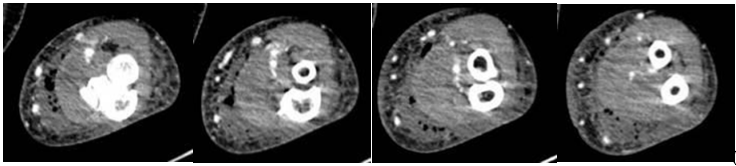

A 72-year-old Caucasian female with Alzheimer’s dementia, hypertension, hyperlipidemia, and hypothyroidism developed progressive swelling and erythema of the left forearm after being bitten by her adult son. She was initially treated at an outside hospital with empiric antibiotics, but worsened, prompting transfer. On arrival, she was hemodynamically stable. Laboratory findings revealed leukocytosis (white blood cell count of 13.2 cells/mcL), hypophosphatemia (1.5 mg/dL), and elevated C-reactive protein (34.19 mg/dL). Computed tomography demonstrated extensive subcutaneous gas and fluid extending from the distal humerus to the wrist (3.2 × 10.5 cm), concerning for NSTI (Fig. 1).

Figure 1: Coronal (a) and axial (b) Computed tomography images of the left forearm demonstrating an extensive subcutaneous fluid collection measuring 3.2 × 10.5 cm and a gas pattern consistent with necrotizing soft-tissue infection. Images progress from proximal to distal.